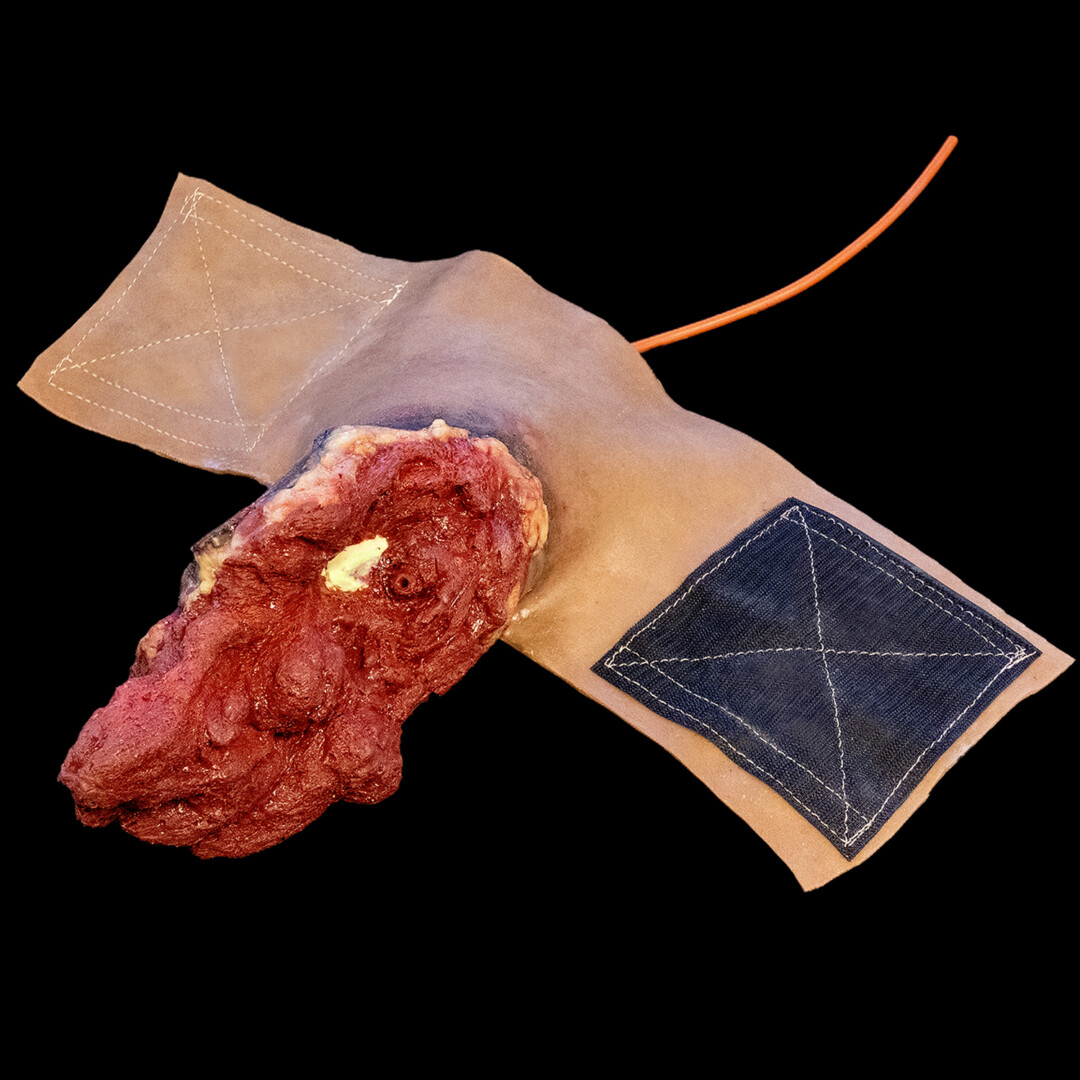

Full Arm Amputation全腕切断オーストリッチインターナショナル。

Partial Arm Amputation Left腕部分切断 左オーストリッチインターナショナル。

四肢再建三重大学形成外科。